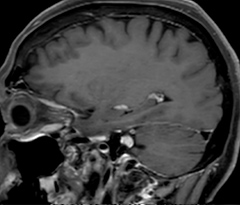

Fast MS protocol with optional sequences

The abbreviated MS protocol for brain is only around 9 minutes, so in case of suspected multiple sclerosis, one or two more advanced sequences may be added, such as PSIR (phase sensitive inversion recovery) or susceptibility-weighted sequences to help us make more confident diagnoses in these inflammatory cases.

In this example, the optional 3D multishot susceptibility weighted sequence with 0.6 mm isotropic voxels is 2 lesions with a central vein sign (arrows) and one lesion with a phase-rim sign (arrowhead). The total scan time, including SmartBrain and axial PD/T2 3mm, is 11:10 min. and is 18:30 min. with the optional 3D PSIR and 3D SWI multishot included.

3D TFE T1

3D FLAIR

DWI image

3D T1w TSE Gd

3D PSIR

3D SWI